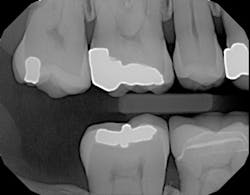

Here's another example of where a patient benefited from this technology's ability to accurately display interproximal caries.1 The patient needed a crown on tooth No. 3, and adjacent tooth No. 2 looked clean on a bitewing x-ray (figure 5).

Figure 5: Bitewing x-ray shows no indication of caries on tooth No. 2Before I began prepping for the crown, I used CariVu. On the images, I saw not only a crack on the tooth that was to be crowned, but also clear caries on the adjacent tooth (figure 6). During treatment, I snapped a picture of the preparation on tooth No. 2 with an SLR extraoral camera (figure 7). I took an additional photo mid-treatment to show how far the cavity had progressed into the dentin. The bitewing didn't show any of this decay. This caries detection technology gives me a great opportunity to tell patients that I found a cavity that we would not have known about until it caused trouble. There is no surprise later and no apologies for missing an early lesion.

Figure 6: CariVu image clearly shows mesial decay on tooth No. 2While some incipient lesions can be put on a "watch list," some should be treated early. Patients don't want to wait until they are in pain or having sensitivity, and that can be avoided by detecting and restoring caries early with smaller fillings that last longer and are less damaging to tooth structure. CariVu has given me another way to prove that I have confidence in my diagnoses. When I have shown x-rays to patients in the past, some have said, "I don't see it, but I trust you." I appreciate their trust, but what I really enjoy is being able to show proof of the caries, treat it, and then follow through.